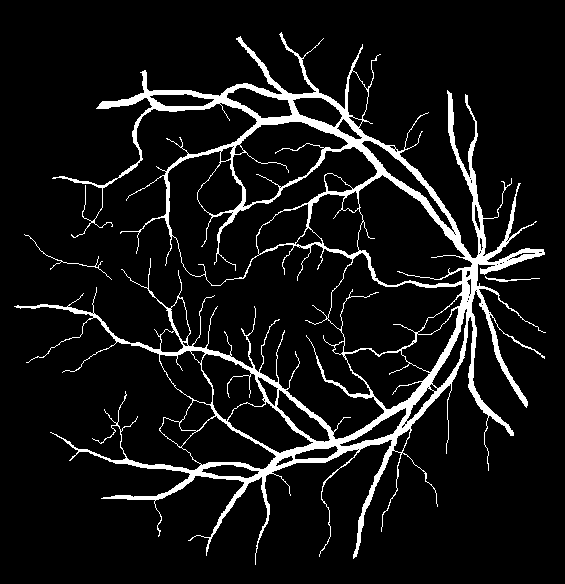

Refer to caption

(a) Ground truth binary mask

(b) Thick vessels binary mask

(c) Thin vessels binary mask

Figure 4: Segregation of ground truth of sample DRIVE image.

After Level-I balancing, the network model is still biased towards the prediction of thick vessel pixels, leaving many thin vessel pixels unidentified. This is because the number of thick vessel’s pixels exceeds those of thin vessel’s pixels. Thus, there is a need to create a balance between the distribution of thick and thin vessel pixels in the training set, termed intra-class balancing. This can be considered another level of balancing on top of Level-I balancing, hence the term Level-II balancing. The balancing obtained from Level-I is further refined by giving an equivalent representation to thick vessel pixels and thin vessel pixels in the training set. The categorization of thick and thin vessel patches requires the segregation of ground truth binary images based on thick and thin vessel pixels. The thick vessels pixels mask is acquired through morphological opening [44] operation, while the thin vessels pixels mask is obtained by subtracting the thick vessel mask from the original ground truth mask. Figure 4 shows the ground truth image of a sample DRIVE image along with the corresponding thick and thin vessel mask images.